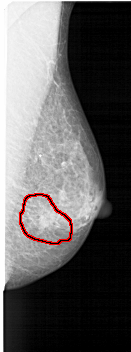

FILE: A_1517_1.RIGHT_MLO.OVERLAY

TOTAL_ABNORMALITIES 1

ABNORMALITY 1

LESION_TYPE CALCIFICATION TYPE PLEOMORPHIC DISTRIBUTION CLUSTERED

LESION_TYPE MASS SHAPE ARCHITECTURAL_DISTORTION MARGINS ILL_DEFINED

ASSESSMENT 5

SUBTLETY 3

PATHOLOGY MALIGNANT

TOTAL_OUTLINES 1

BOUNDARY